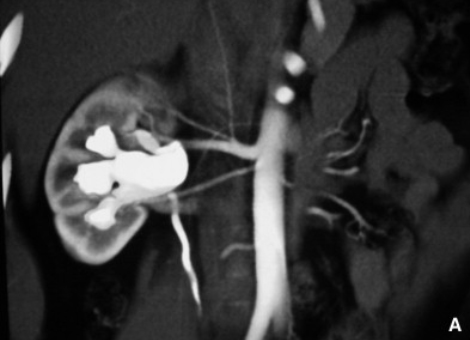

Diagnostic

La première étape consiste souvent en une échographie rénale, qui montre

la dilatation du bassinet. Un scanner de l’appareil urinaire (uro-scanner) ou

une scintigraphie rénale (MAG3) peuvent compléter l’évaluation pour mesurer

l’importance de l’obstruction et son retentissement sur le rein.

pour se manifester plus tôt. Certains facteurs, comme des vaisseaux sanguins

aberrants, peuvent aussi comprimer la jonction pyélo-urétérale.